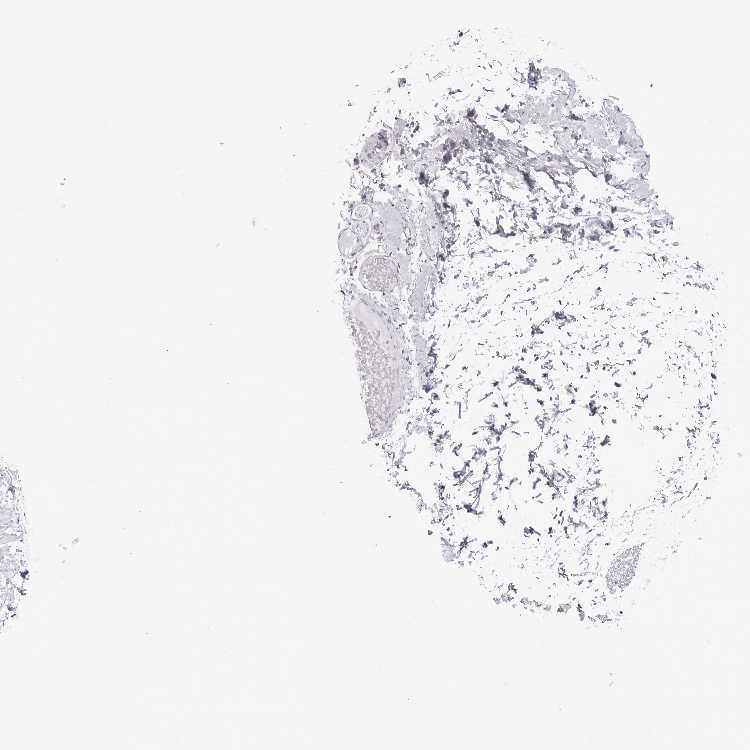

ADIPOSE TISSUE - Antibody stainingi

Antibody staining in the annotated cell types in the current human tissue is reported as not detected, low, medium, or high, based on conventional immunohistochemistry profiling in selected tissues. This score is based on the combination of the staining intensity and fraction of stained cells.

Each image is clickable and will lead to virtual microscopy that enables deeper exploration of all samples and also displays staining intensity scores, fraction scores and subcellular localization as well as patient and tissue information for each sample.

Antibody HPA043706Antibody HPA044763Antibody CAB024963

Adipocytes Not detectedNot detectedNot detected